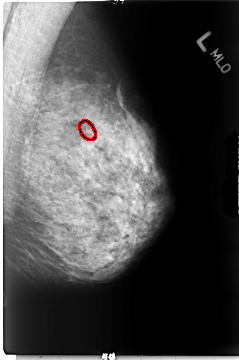

B_3044_1.LEFT_MLO

FILE: B_3044_1.LEFT_MLO.OVERLAY

TOTAL_ABNORMALITIES 1

ABNORMALITY 1

LESION_TYPE CALCIFICATION TYPE PLEOMORPHIC DISTRIBUTION CLUSTERED

ASSESSMENT 4

SUBTLETY 4

PATHOLOGY MALIGNANT

TOTAL_OUTLINES 1

BOUNDARY

LEFT_MLO LINES 4680 PIXELS_PER_LINE 3096 BITS_PER_PIXEL 12 RESOLUTION 50 OVERLAY